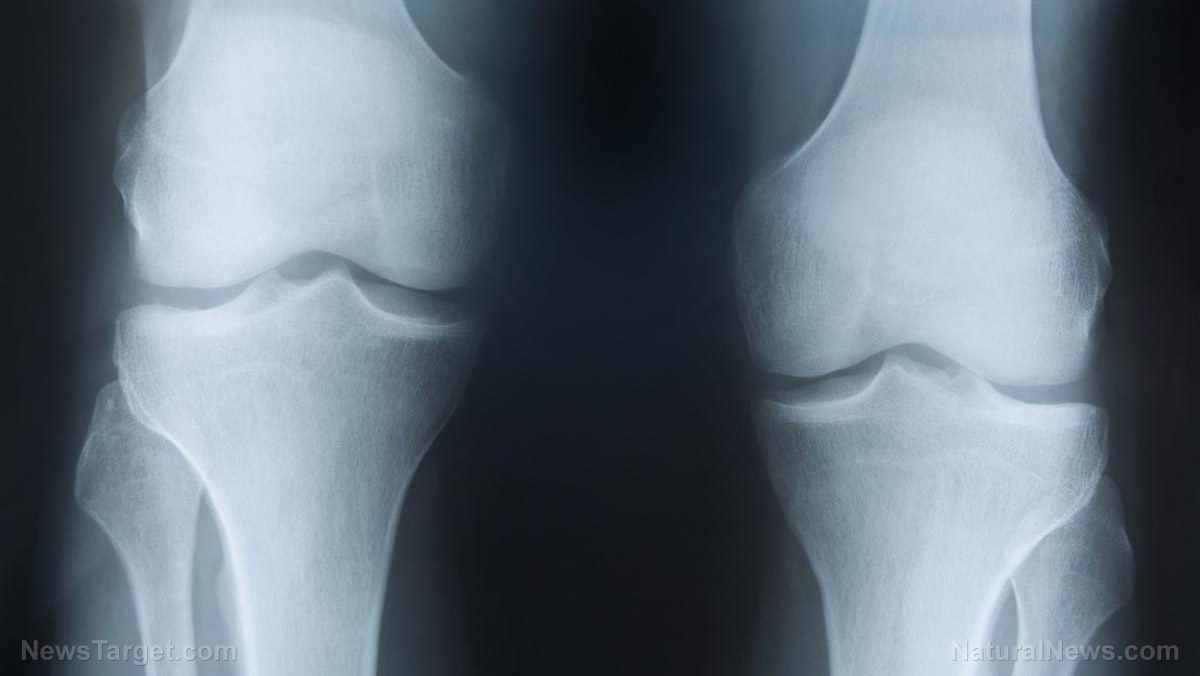

Osteoarthritis of the knee is one of the most pervasive and worrisome conditions that seems to affect many older individuals. This should be no surprise, since it is well-known that millions of people deal with some form of arthritis every single day. That's why the search for better and more effective cures is still ongoing.

As part of this search, a group of researchers from the United States has recently conducted a study on the effects of using bone growth stimulators for the treatment of osteoarthritis of the knee. The researchers found the motivation to explore the possibilities from the fact that there is evidence that osteoarthritis is mainly a disease of subchondral bone, which can be changed by using bone growth stimulators to change the contained fibrous tissue.